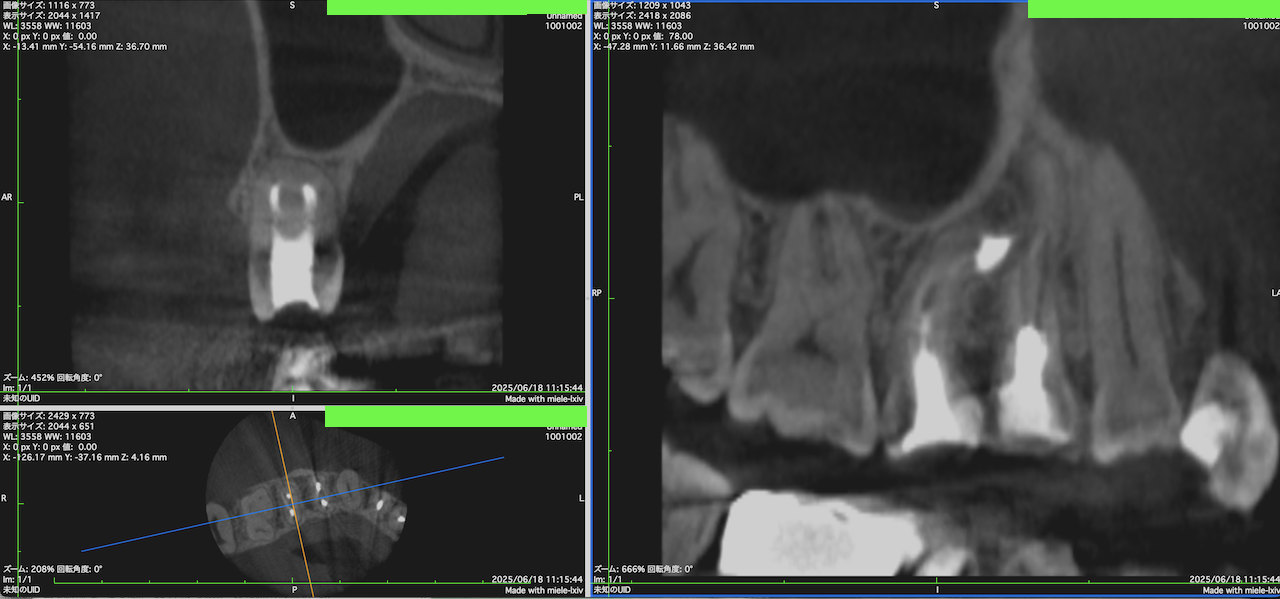

#4 Apicoectomy 1.5yr recall(2025.6.18)

術前・術後を比較した。

上部構造は1.5年間,プロビジョナルレストレーションであったが治癒した。

経過観察も終診でいいだろう。